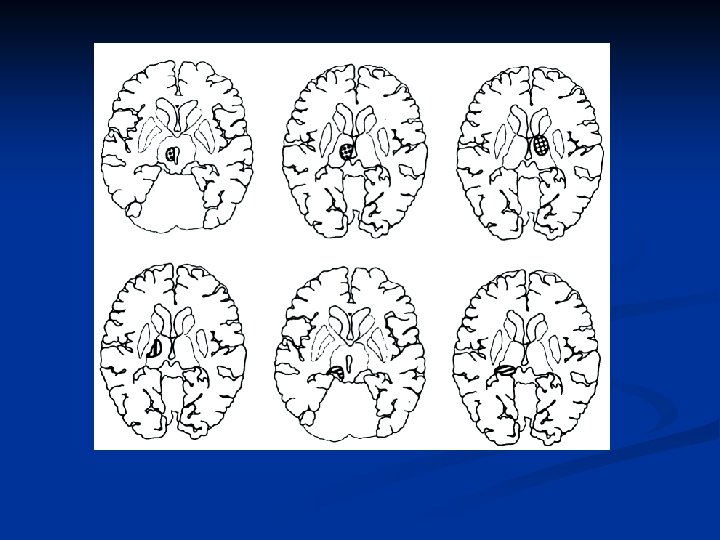

MRI Findings Case 1 Case 2 Case 3